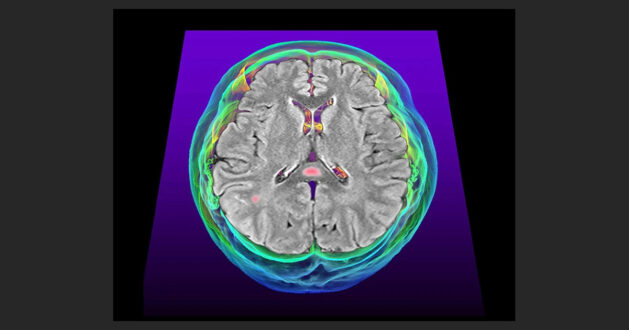

COVID-19’un bazı bilişsel semptomlarından sızdıran kan-beyin bariyeri ve inflamasyon sorumlu olabilir.

Koku kaybı, baş ağrıları, hafıza sorunları: COVID-19, günlük işleri zorlaştıran rahatsız edici bir nörolojik semptom fırtınasına neden olabilir. Yeni araştırmalar bu semptomların altında beyindeki inflamasyonun yatabileceğine dair kanıtlar sunuyor.

Araştırmacılar, COVID-19’un neden olduğu beyin sorunlarının suçlusunu aramaya başladığında, inflamasyon hızla başlıca şüphelilerden biri oldu. Bunun nedeni, vücudun davetsiz misafirlere karşı salgıladığı bağışıklık hücreleri ve kimyasallara bağlı inflamasyonun, HIV gibi başka virusların neden olduğu bilişsel semptomlarla bağlantılı olmasıdır. SARS-CoV-2 vücutta güçlü bir bağışıklık tepkisine yol açar, ancak beyin hücrelerinin bu tepkiye katkıda bulunup bulunmadığı ve eğer öyleyse nasıl olduğu belirsizdi.

Charité – Berlin Üniversitesi Tıp Fakültesi’nden nöropatolog Helena Radbruch ve meslektaşları, COVID-19’dan ölen insanlardan alınan beyin örneklerini inceledi. SARS-CoV-2 ile infekte olmuş herhangi bir hücre bulamadılar. Ancak bu insanların belirli beyin bölgelerinde, diğer nedenlerden ölen insanlara göre daha fazla bağışıklık aktivitesi olduğunu saptadılar. Bu olağandışı aktivite, koku alma duyusuyla ilgili olan koku alma soğanı ve nefes alma gibi bazı bedensel işlevleri kontrol eden beyin sapı gibi bölgelerde fark edildi. Bu durum yalnızca virusa yakalandıktan kısa süre sonra ölen insanların beyinlerinde görüldü.

Radbruch’a göre bu gözlemler, COVID-19’un beyin dışında neden olduğu iltihaplanmanın infeksiyonun erken dönemlerinde belirli beyin bölgelerinde bağışıklık tepkisini tetiklediğini ve bunun da nörolojik semptomlara yol açabileceğini akla getiriyor. Ekip, nöroinflamasyonun devam etmesi durumunda, infeksiyondan sonra aylarca veya yıllarca sürebilen karmaşık semptomlar topluluğu olan uzun COVID ile bağlantılı beyin semptomlarına yol açabileceğinden şüpheleniyor. Bulgular Nature Neuroscience dergisinde yayımlandı.